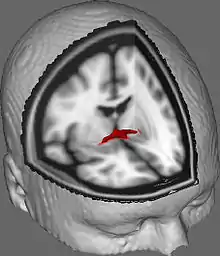

![]() Tractography of anterior commissure | |